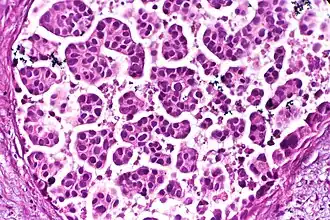

-

Nests: islands of cells of similar type. -